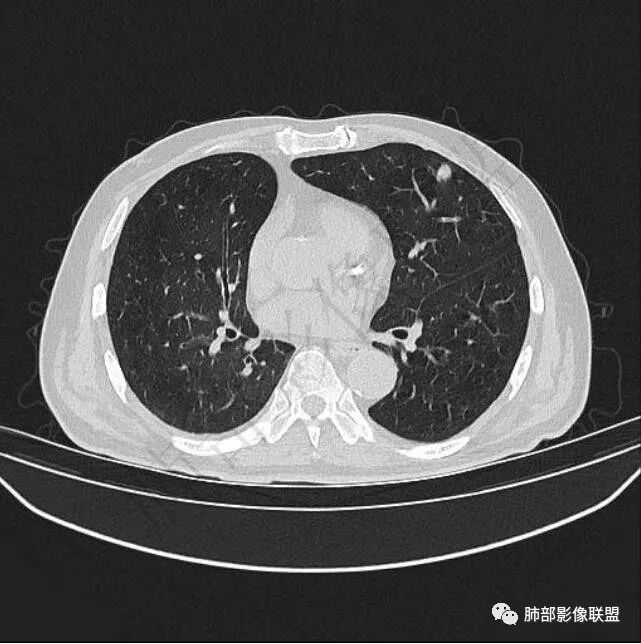

9个月后病灶明显增大,边缘较平直,部分膨隆,锁扣样外观,仍旧缺乏典型深分叶及张力,未见胸膜凹陷。

再1个多月后病灶继续增大,较明显不均匀强化,肺门一侧见低密度区。病灶边缘相对不清,可见毛刺。

三.病程脉络相当清楚,即病灶进行性增大,易想到新生物或转移瘤,但经验上分析增长速度显然太快,尤其是对于原发肺腺癌或者肺鳞癌而言,单发转移瘤也较少这样的进展速度。